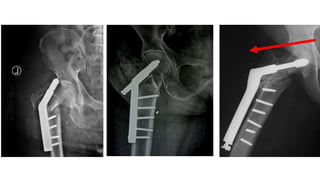

Unstable pattern (31A2)

Unstable pattern (31A3)

DHS CMN

DHS

• Stable / simple fracture only

DHS vs CMN for 31A2 & 31A3

• CMN has

• Lower blood loss

• Shorter operative time

• Lower fixation failure

• Less superficial infection

• Less non union

• Better functional score

• CMN for 31A1?